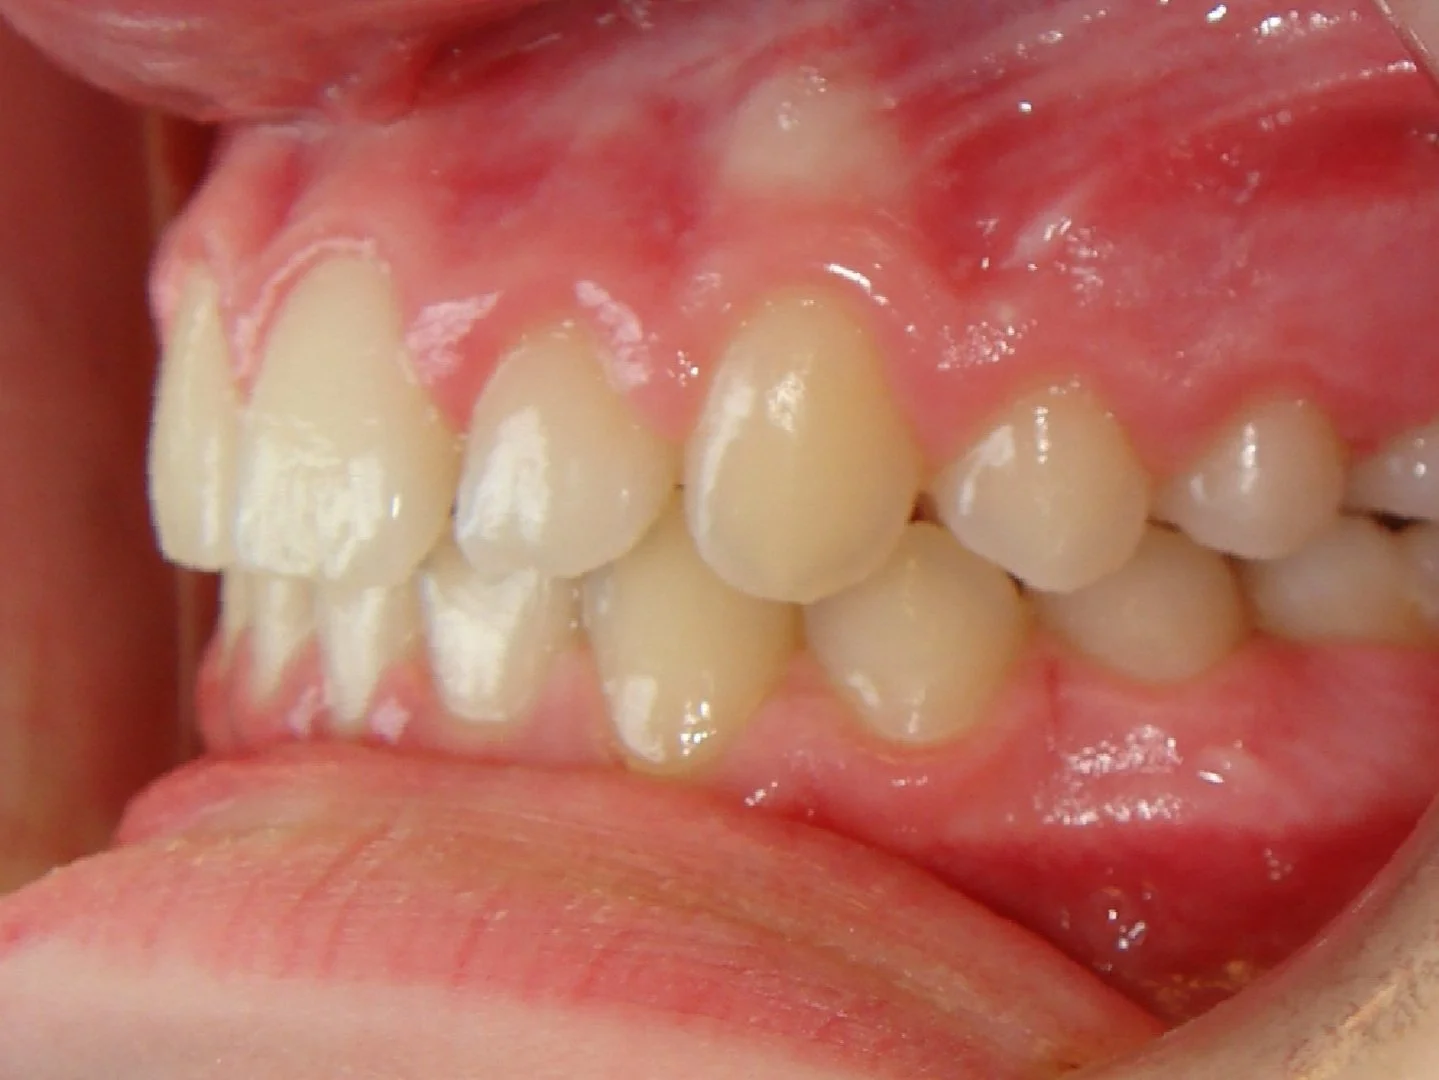

Case #1: Excess Overjet / Overbite & Crowding

Close-up of a person's mouth with misaligned teeth, overbite and gums.

Before

This 10 year old girl had crowding of her upper and lower teeth, and an extreme overjet and overbite. Her case was treated over 2 years with braces and elastics.